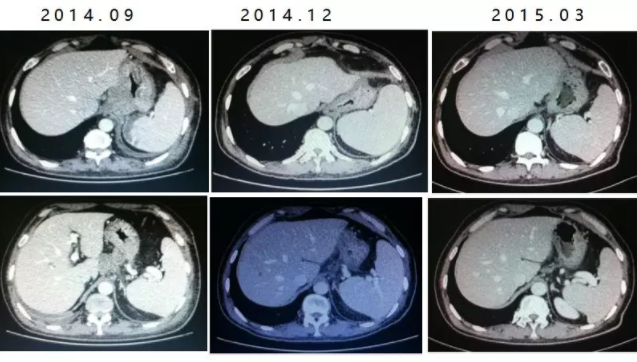

术后(2014.09.24~2015.02.02)给予8周期的“XELOX+赫赛汀”联合治疗。

2周期时达到PR,4、6、8周期确认PR。

2015.03~2015.07给予6周期的“卡培他滨+曲妥单抗”维持治疗(周围神经毒性为2级)。

2015.07复查CT:贲门胃体及胃体上部胃壁增厚较前明显,PD。